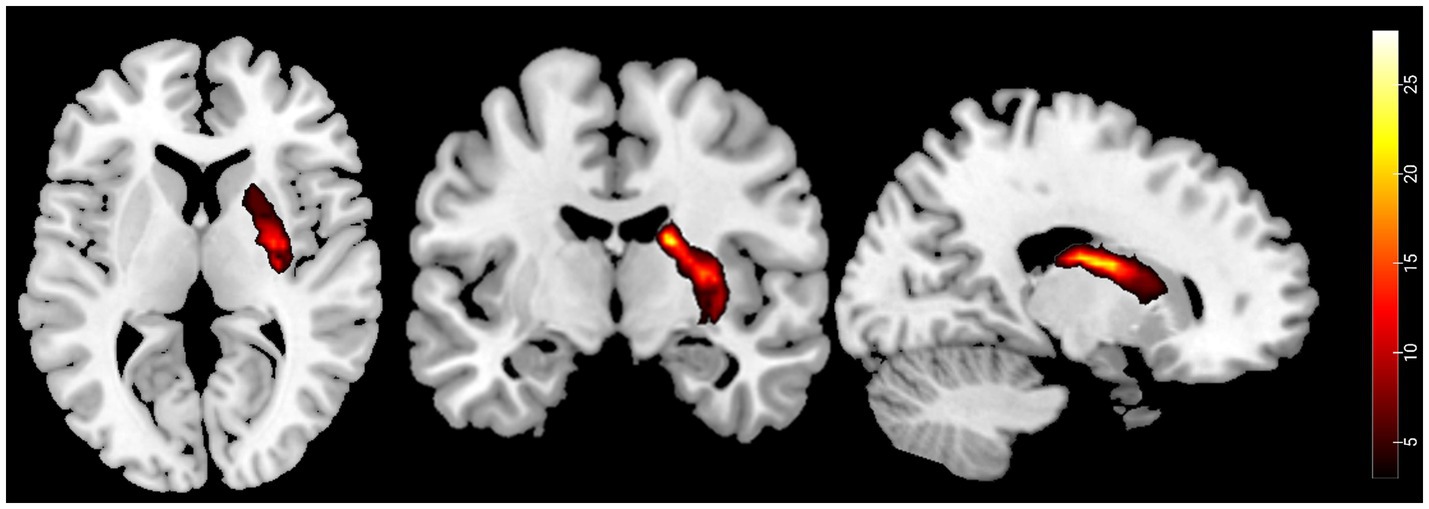

The stroke lesion probability map calculation

First, an experienced neuroradiologist used MRIcron software to precisely identify and manually delineate each stroke patient’s lesion on the original T1-weighted images, creating a customized lesion mask for each patient. Second, these T1-weighted images were spatially normalized to MNI space. The lesion masks were then co-registered to MNI space using the normalization parameters. Finally, a group-level lesion probability map was generated by combining all lesion masks in MNI space and dividing by the number of patients. The stroke lesion probability map is shown in Figure 2.

Figure 2. Probability maps of capsular stroke lesions. Color bar represents the lesion probability across patients.